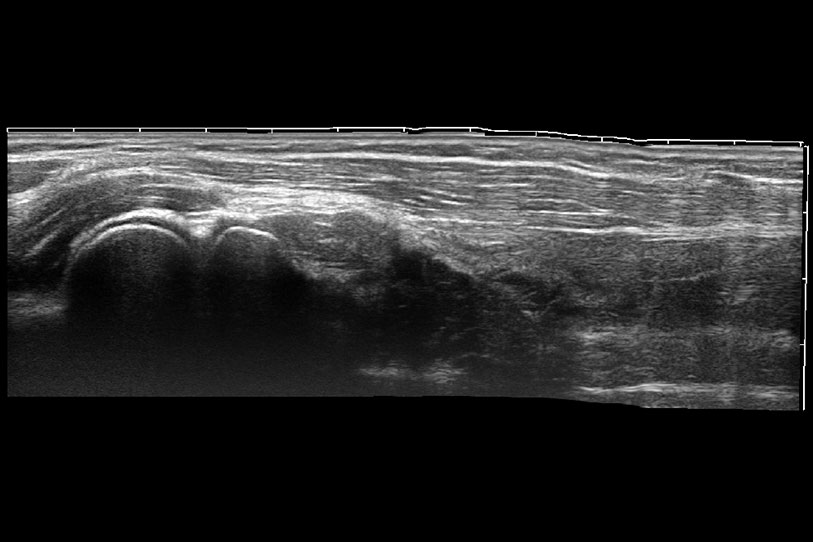

通過色彩血流和實(shí)時(shí)寬景相結(jié)合,可觀察到完整的靜脈或動(dòng)脈的血流,方便醫(yī)生檢查。實(shí)時(shí)掃查過程中,如有任何操作失誤也可以很容易地進(jìn)行回掃擦除,而不會(huì)中斷掃查。

為精細(xì)結(jié)構(gòu)及組織邊緣提供高清晰度的圖像和更大的成像視野。幫助減輕醫(yī)生的用眼疲勞,快速精準(zhǔn)獲得測(cè)量的數(shù)據(jù)。

ProPet 70 全新的動(dòng)物超聲智能軟件和豐富的探頭群,為動(dòng)物醫(yī)生提供了高清晰度和精細(xì)分辨率的圖像,無論在寵物、馬科、畜牧還是實(shí)驗(yàn)室動(dòng)物等應(yīng)用中都可以輕松應(yīng)對(duì),為您的日常工作帶來滿意的體驗(yàn)。